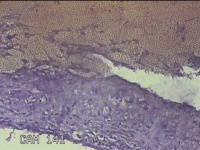

左卵巢囊肿

性别

女

年龄

47岁

临床诊断

左附件囊肿

一般病史

不规则阴道流血20余天。

标本名称

大体所见

灰白暗红色囊壁样组织4.3x1.3x0.3cm一块,表面光滑,因已切开,囊内容物已流失,囊壁厚0.1cm。

图1

良性病变。